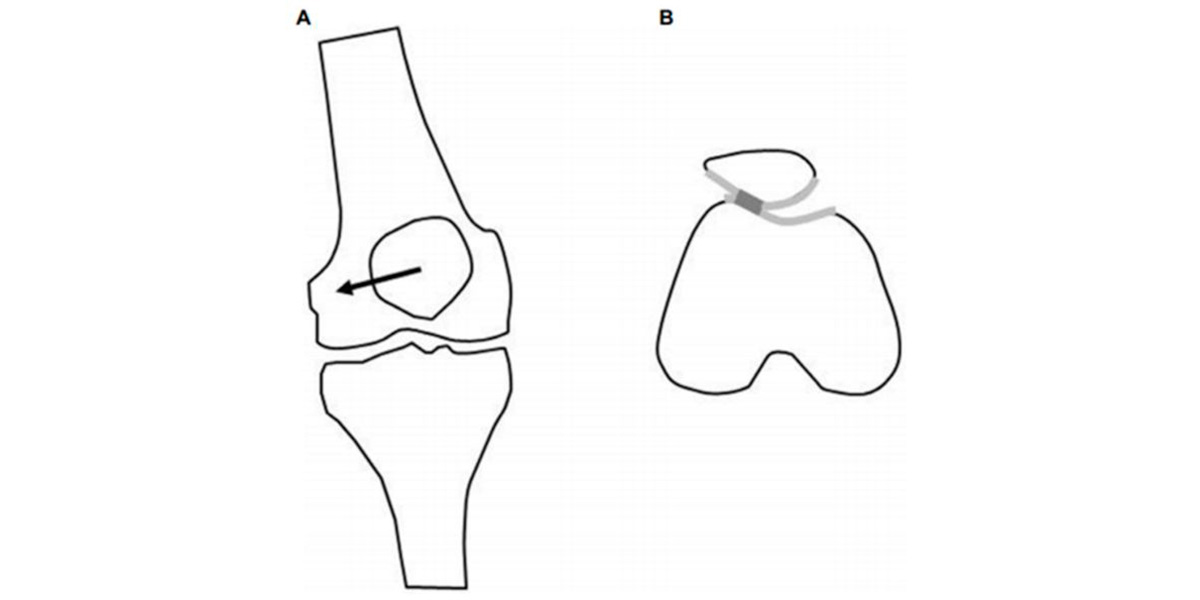

A principal manifestação do joelho é a do desvio patelar:

Este desvio verifica-se quando realizamos exercício físico, por exemplo, no denominado valgo dinâmico funcional, onde o fémur ou a tíbia (ou ambos) rodam internamente e fazem com que o joelho de desloque «para dentro» (adução);

Uma posição na qual não deveria estar, e que aumenta radicalmente a resistência por atrito, degradando a cartilagem.

Figura IV. Representação gráfica de um valgo funcional no joelho.

A articulação do joelho, que está sujeita a esta posição durante muito tempo (por exemplo, os praticantes de desporto), acaba por deslocar a rótula para o exterior, dificultando o controlo muscular sobre a articulação e causando uma grande instabilidade sobre o joelho, o que aumenta o rico de sofrer uma lesão aguda (como uma luxação ou um deslocamento), e/ou crónica (tendinite, desgaste da cartilagem, osteoartrite…).

Esta situação denomina-se de desvio patelar.

Figura V. Representação gráfica do deslocamento patelar na vista frontal (A) e axial (B).